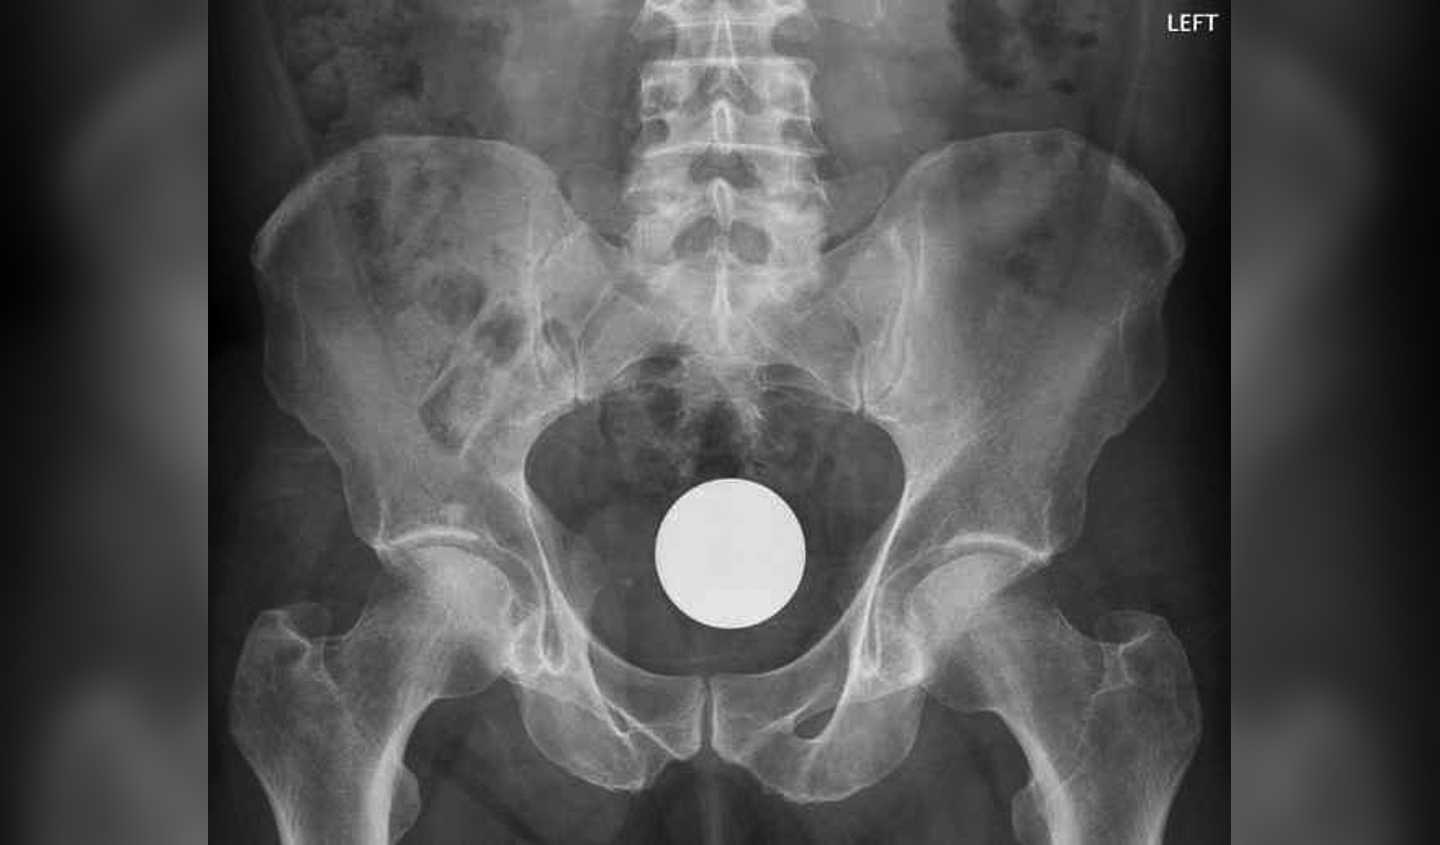

Een trillende vibrator, komkommer of hardgekookte eieren in de endeldarm – op de Spoedeisende Hulp kijken ze er niet vreemd van op. Jaarlijks melden zich een paar ho..